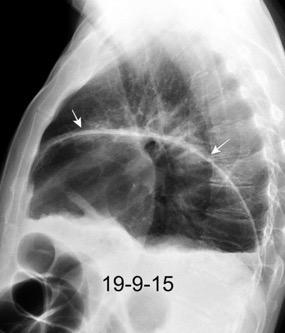

Parálisis frénica transitoria tras cirugía de válvula aórtica

Parálisis frénica transitoria post cirugía cardiaca (10%).

Puede acompañarse de atelectasia del LII.

Benjamin JJ et al. . Left lower lobe atelectasis and consolidation following cardiac surgery: the effect of topical cooling on the phrenic nerve. Radiology 1982